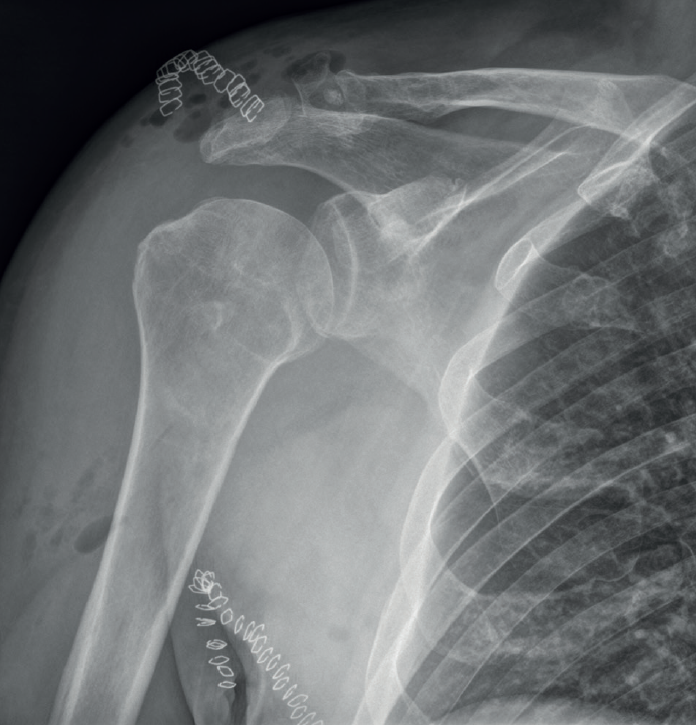

After transfer of the latissimus dorsi, arthrotic degeneration of the joint is comparable to that seen with non-surgical treatment, though progression is slower, and the increase is limited to 1 or 2 stages of the classification of Hamada(13)(Figures 4 and 5).